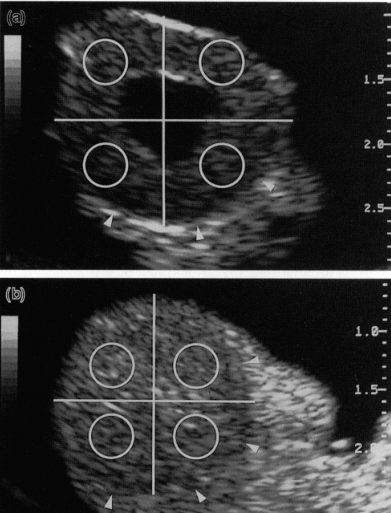

上图中具有中心腔 (a) 或无腔 (b) 的牛黄体的图像分析技术。黄体与间质由箭头划分。每个黄体的图像被分成四个相等的象限。通过放置一个覆盖每个象限大约 20% 的测量点(圆圈)来测量像素值。像素值是落在测量点下的所有像素的灰度值的平均值。超声图像上的刻度···